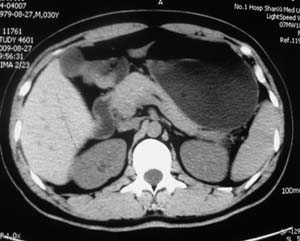

以下是引用子期在2010-3-19 20:47:00的发言:[br]血管畸形的ct增强应该有明显强化,本例并不相符合。本例双肾局部的略低密度影,累及肾盂,局部皮质明显变薄、内陷,增强扫描有轻度的强化,应考虑为炎性病变,患者为年轻男性,累及双肾的感染以结核较常见,可以没有明显的临床症状,尿中有时候也并不能查出什么;肾脓肿常有明显感染中毒症状,本例不符,另外一般的肾盂肾炎或肾小球肾炎通过小便就可确诊,其它还不能排除的是黄色肉芽肿性肾盂肾炎,然而单凭ct一般也很难鉴别。